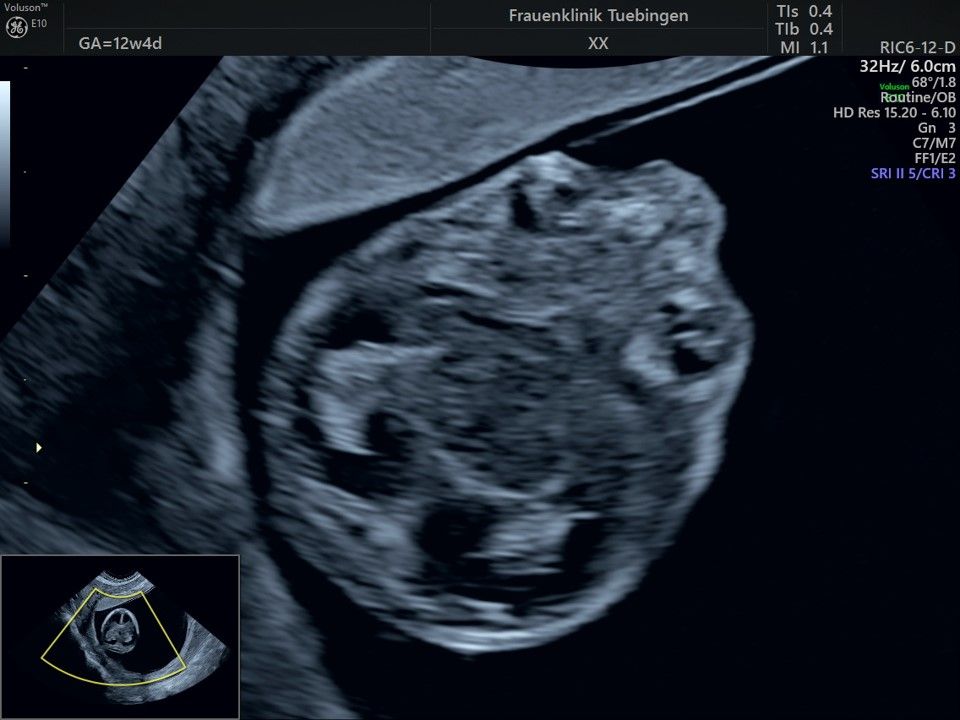

Im Rahmen des Ersttrimester-Screenings untersuchen wir die Organe des Feten mittels Ultraschall. Dabei machen wir auch gerne ein Bild für Sie.

Obwohl der Fet zu diesem Zeitpunkt erst zwischen 5 und 8cm groß ist, lassen sich bereits etwa die Hälfte aller schwerwiegenden Fehlbildungen erkennen bzw. ausschließen. Sollten wir eine Auffälligkeit sehen, werden wir mit Ihnen den Befund und das weitere Vorgehen ausführlich besprechen.

Fetale Anatomie